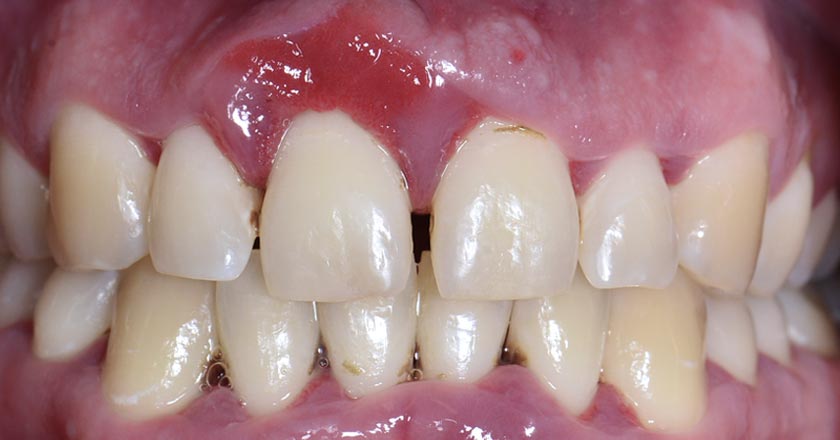

Gum Disease - Before And After

Gum disease scaling and root planing – before treatment